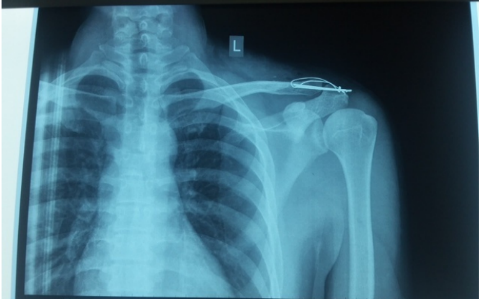

Hình ảnh kết hợp xương khớp cùng đòn bằng vít quạ - đòn

5.2.2.1. Bắt vít quạ - đòn, vòng chỉ

Kỹ thuật này là bắt vis cố định từ xương đòn xuống mỏm quạ hoặc qua nội soi buộc cố định vòng chỉ siêu bền từ xương đòn xuống mỏm quạ. Nhược điểm là cần phẫu thuật tháo vít về sau, vòng chỉ có thể cắt xương đòn và nền mỏm quạ. Phương pháp này cũng chỉ áp dụng được cho trật khớp cùng  đòn cấp tính.